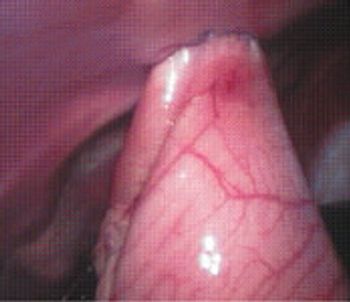

Globe removal is indicated in patients with blind, painful eyes or patients with nonresectable intraocular tumors.